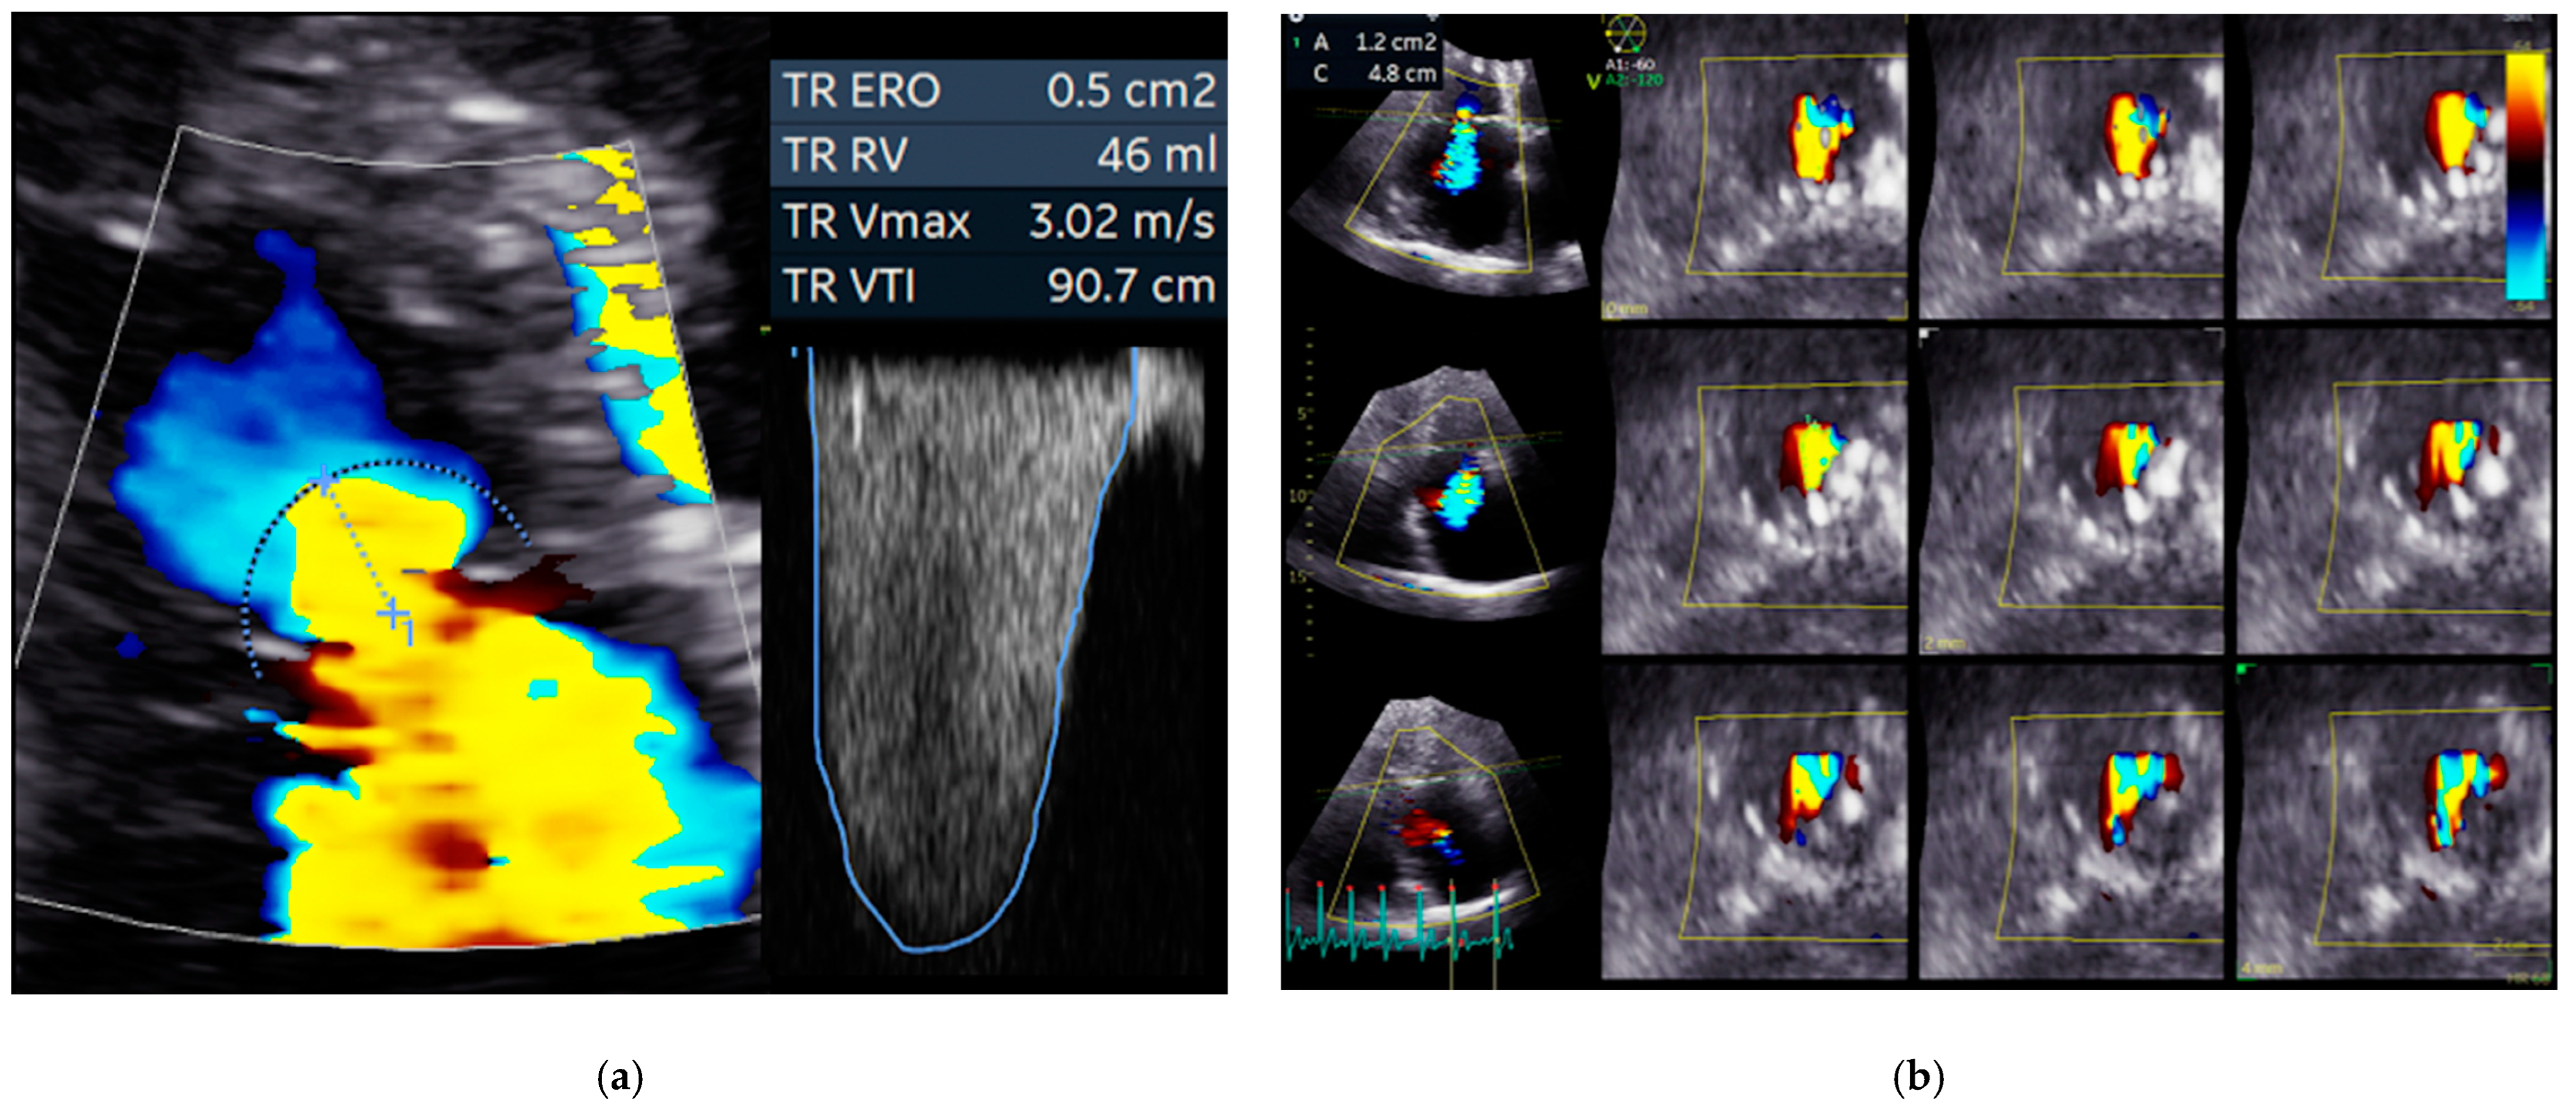

3.1. Echocardiography